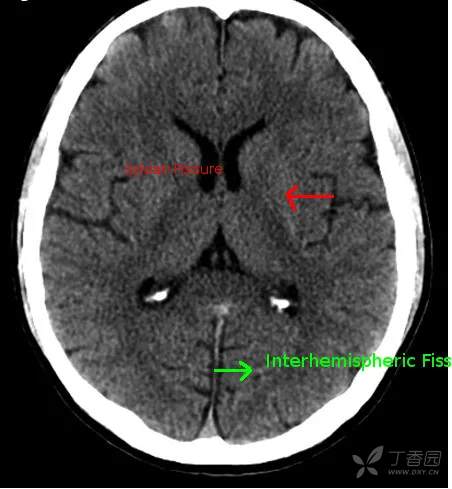

大脑纵裂池

大脑纵裂池 cistern of cerebral longitudinal fissure (interhemispheric fissure cistern)位于两侧大脑半球之间的大脑纵裂内,内有大脑镰插入,故此池分为左右两部。

该池底部绕于胼胝体周围,称为胼胝体体周池,向前下延为终板池,向后下续于大脑大静脉池。

大脑纵裂池在不同横断面上的表现各异。例如,在胼胝体以上层面中所见为大脑纵裂池全长;在胼胝体出现的层面上大脑纵裂池分为前后两段,分别位于胼胝体断面的前后方;在较低的鞍上池层面则只见大脑纵裂池前段。

CT

MRI T2